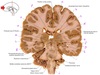

1

Q

a

body of corpus callosum

2

b

Anterior horn of lateral ventricle

3

c

Septum pellucidum

4

d

5

e

6

f

7

g

Putamen

How well did you know this?

Not at all

Perfectly

8

h

Nucleus accumbens